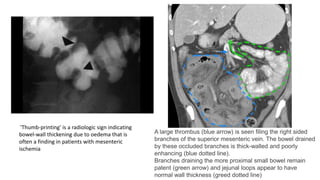

A large thrombus (blue arrow) is seen filing the right sided

branches of the superior mesenteric vein. The bowel drained

by these occluded branches is thick-walled and poorly

enhancing (blue dotted line).

Branches draining the more proximal small bowel remain

patent (green arrow) and jejunal loops appear to have

normal wall thickness (greed dotted line)

''Thumb-printing' is a radiologic sign indicating

bowel-wall thickening due to oedema that is

often a finding in patients with mesenteric

ischemia